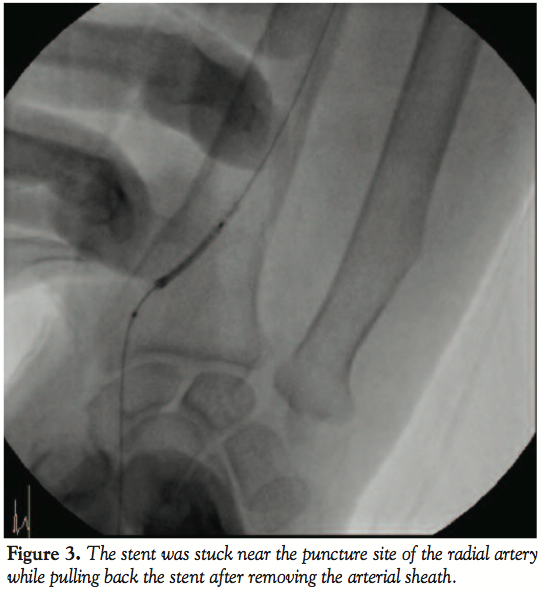

After that, we tried to pull back the unexpanded stent and balloon catheter into the guiding catheter but failed to enter completely. The guiding catheter and the all stent system, which was partially entered and stuck in the guiding catheter, were carefully withdrawn together into the distal radial artery. After removal of guiding catheter, we tried to withdraw the stent into the arterial sheath, but failed. Finally, while pulling back the stent after removal of the arterial sheath, the stent was stuck near the puncture site of the radial artery (Figure 3). Under

local anesthesia in the catheterization laboratory, a vascular surgeon incised the skin, cut down the radial artery, retrieved the distorted stent successfully, and repaired the radial artery. Five days later, the proximal LAD lesion was treated successfully with stent through the right femoral artery and the repaired radial artery was patent in the antegrade angiogram (Figure 4). The patient was discharged 2 days later with an improvement of anginal symptom and no complication in the arm and hand (Figure 5).